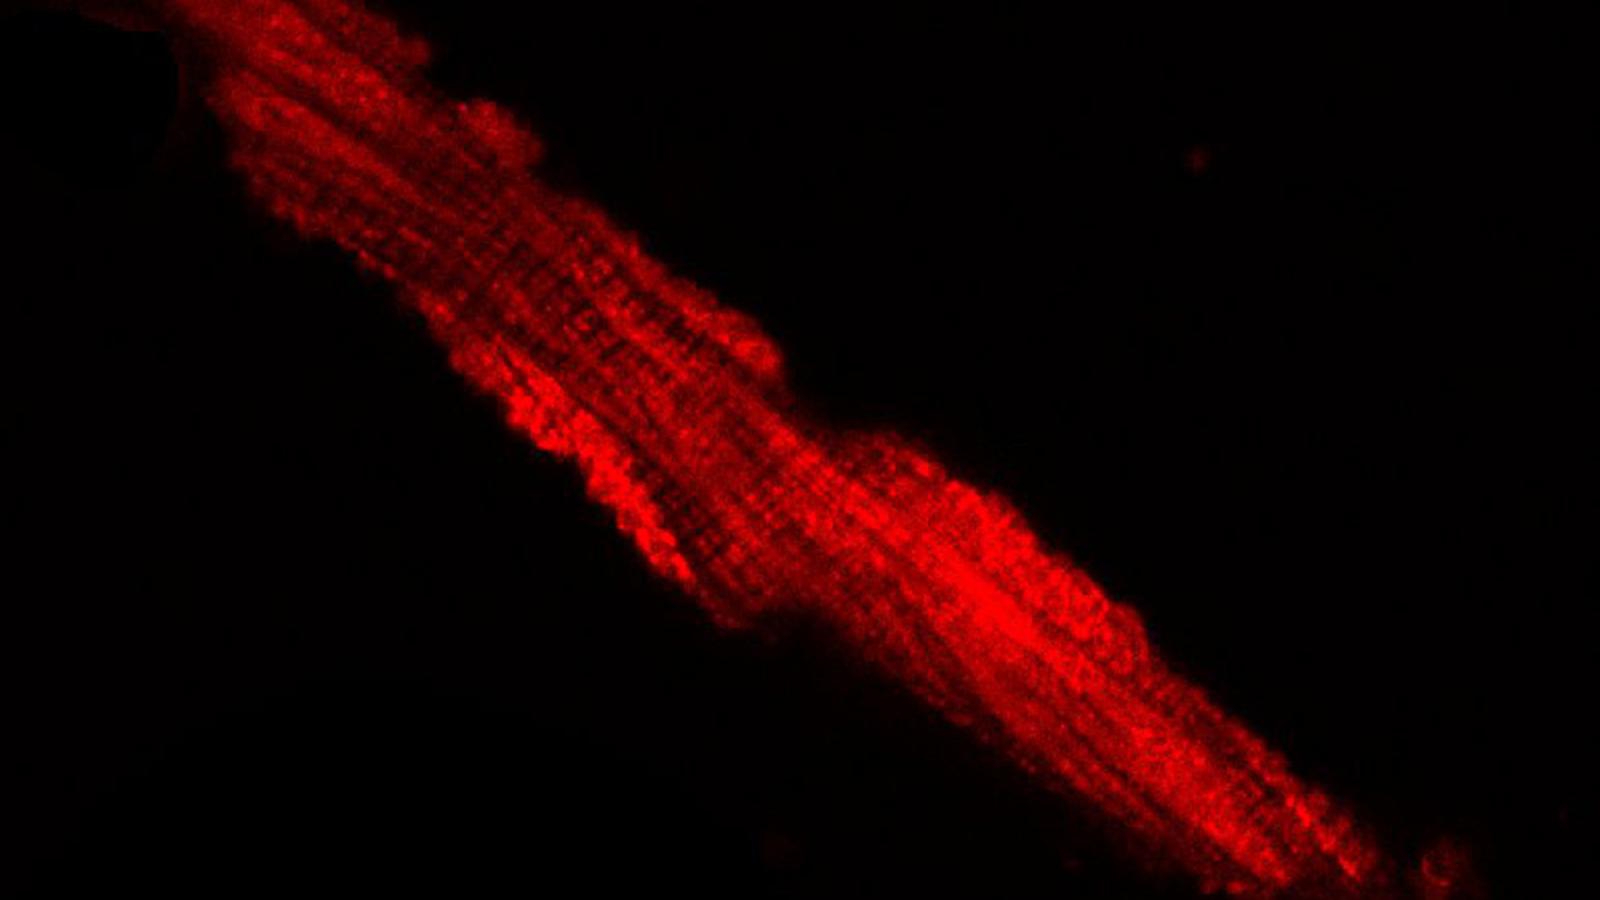

The Marx Lab studies the regulation of ion channels by macromolecular complexes. We have demonstrated that specific sequences within the ion channel (leucine zippers) recruit regulatory proteins, which modulate the ion channel function in normal and pathologic conditions. The laboratory is now focused on understanding the molecular components and functional implications of macromolecular complex formation of the large conductance calcium-activated potassium channel (BKCa, maxi-K) and the L-type voltage gated calcium channel. The laboratory utilizes both molecular biologic and electrophysiologic (planar lipid bilayer, patch clamp) techniques to elucidate these fundamental processes and emphasizes the links between these fundamental molecular processes and systems function. To date our work has had significant impact in understanding the triggers of fatal cardiac arrhythmias and mechanical dysfunction in heart failure. Present experiments are very likely to impact our understanding of control of peripheral blood pressure by the sympathetic nervous system.